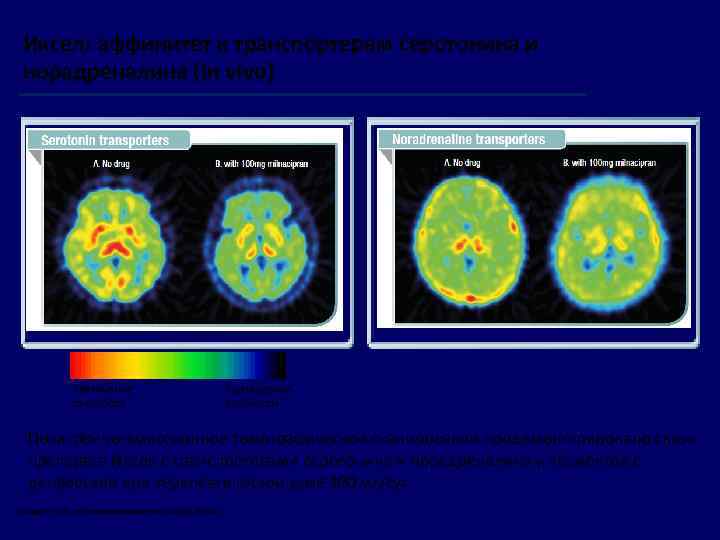

Иксел: аффинитет к транспортерам серотонина и норадреналина (In vivo) Увеличение плотности Уменьшение плотности Позитронно-эмиссионное томографическое сканирование продемонстрировало связь препарата Иксел с транспортерами серотонина и норадреналина у пациентов с депрессией при терапевтической дозе 100 мг/сут. 1. Nogami T et al. Int J Neuropsychopharmacol 2013; 16: 937 -43.